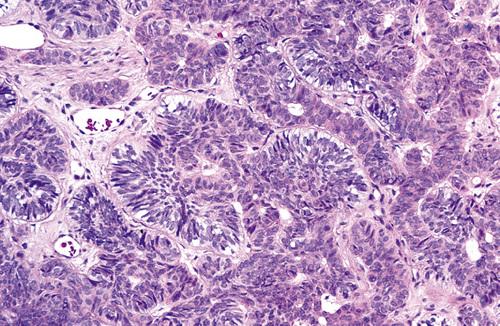

Histopathologic Features

- lined by squamous epithelium of varying thickness

- uneven hobnail and sometimes papillary surface

- mucin-producing goblet cells in the surface layer

- glandular, ductlike spaces within the epithelial lining

- mucicarmine-positive fluid within spaces

The cyst is lined by stratified squamous epithelium that exhibits surface columnar cells with cilia. Numerous microcysts containing mucinous material are present.

glandular odontogenic cyst